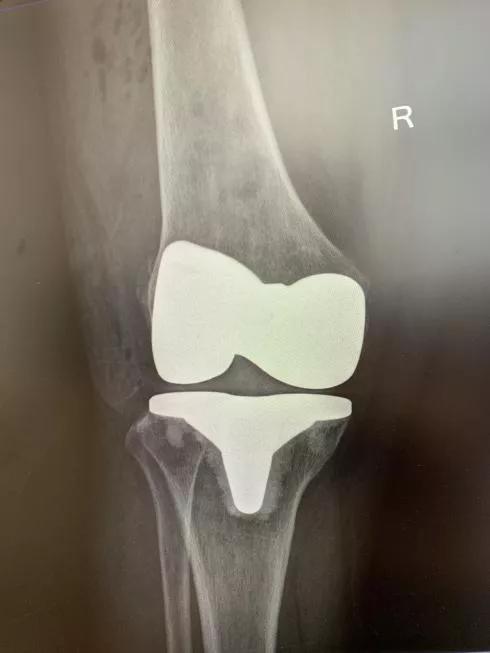

▲术后 X 光片显示:右髋假体、右膝假体位置角度放置与术前规划一致。